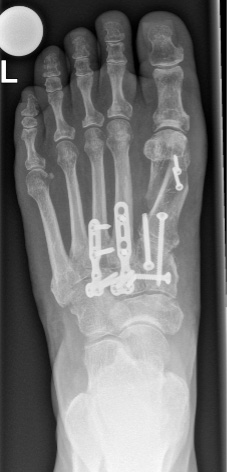

Führt die konservative Therapie nicht zum Erfolg, kommt eine Operation in Frage. Bei störenden Osteophyten und nur geringfügiger Arthrose kann ein Abtragen des Knochens zum Erfolg führen. Ist die Arthrose fortgeschritten, fällt die Wahl meistens auf eine Versteifung (Arthrodese). Die betroffenen Gelenke werden dazu durch Schrauben oder Platten fixiert. Da die Mittelfussgelenke wenig zur Gesamtbewegung des Fusses beitragen, ist der Einfluss der Versteifung auf den Bewegungsumfang des Fusses gering. Dadurch ist gehen auch nach der Versteifung weiterhin gut möglich.

Eine Ausnahme bilden jene Gelenke, die zur kleinen Zehe und der daneben ziehen. Sie sind wichtig für die Anpassung des Fusses an unebenes Gelände und sollten deshalb in der Regel nicht versteift werden. Ist die Arthrose hier fortgeschritten, ist die Entfernung des Gelenks als letztes Mittel möglich *. Bei einer Versteifung sollte ausserdem überprüft werden, ob eine Fehlstellung im Mittelfuss vorliegt, sodass diese mitkorrigiert werden kann. Das Gangbild ändert sich aufgrund der geringen Beweglichkeit des Mittelfusses nur geringfügig *.

Damit die Versteifung richtig ausheilen kann, muss der Fuss nach der Operation ruhiggestellt werden. In den ersten 6 Wochen ist deshalb ein Unterschenkelgehgips und Stockentlastung notwendig. Danach erfolgen eine Röntgen- und eine CT-Aufnahme zur Beurteilung des Heilungsfortschritts. Je nachdem wie der Knochen bereits zusammengewachsen ist, muss ein anderer Gips oder ein Schuh mit harter Sohle für weitere 6 Wochen getragen werden.